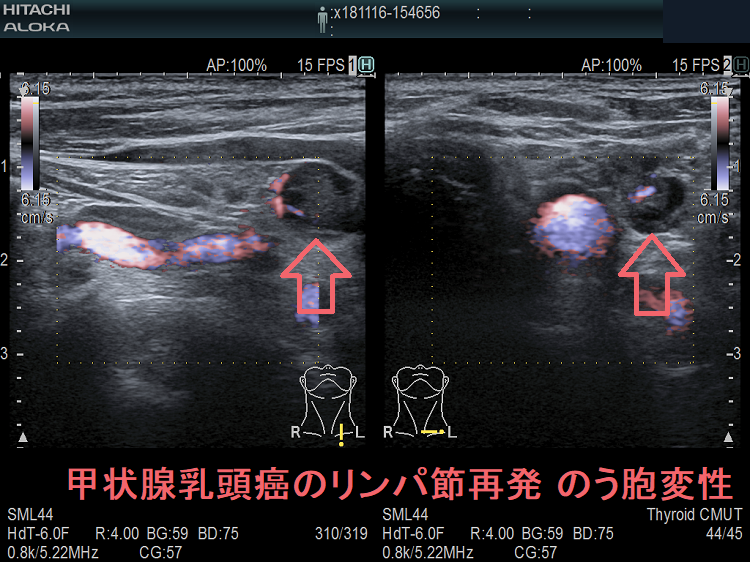

甲状腺乳頭癌鎖骨上窩リンパ節転移再発 のう胞変性(嚢胞変性)

甲状腺乳頭癌の左鎖骨上窩 リンパ節再発 のう胞変性 超音波(エコー)画像

甲状腺乳頭癌の左鎖骨上窩 リンパ節再発ですが、のう胞変性(嚢胞変性)をおこしているため、正常なリンパ節で無いのは一目でわかります。

甲状腺乳頭癌の左鎖骨上窩 リンパ節再発 のう胞変性 超音波(エコー)画像ドプラーモード

甲状腺乳頭癌の甲状腺乳頭癌の左鎖骨上窩 リンパ節再発 のう胞変性(嚢胞変性) 超音波(エコー)画像 ドプラーモード